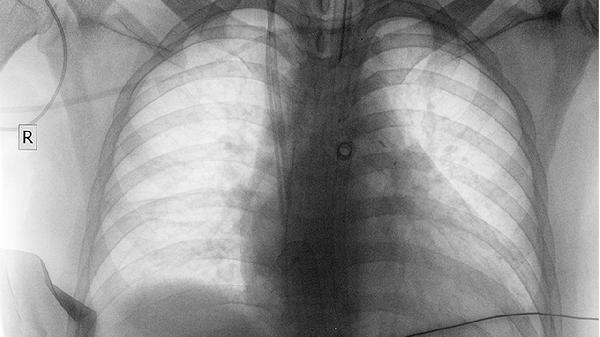

肺结核、慢阻肺、肺纤维化等疾病会导致肺部持续炎症反应,长期刺激可能诱发细胞癌变。患者需规范治疗原发病,避免感染加重肺损伤,同时监测肺部结节变化。